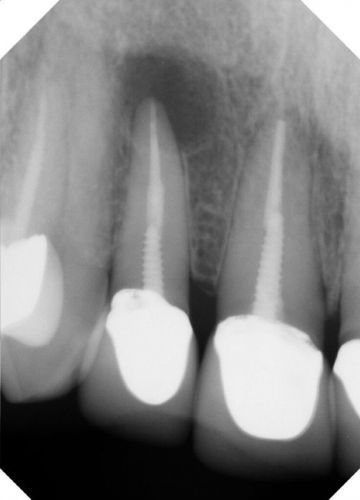

Рентгеновские снимки кариеса корня зуба

Раздел: Визуальные уроки